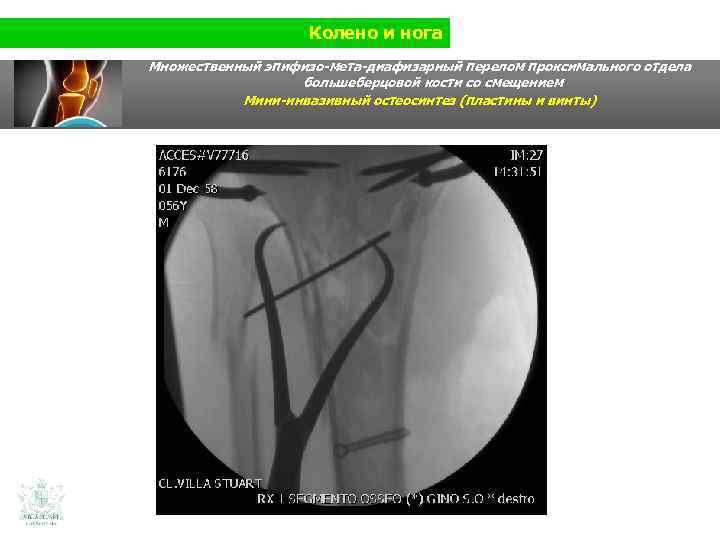

Колено и нога Множественный эпифизо-мета-диафизарный перелом проксимального отдела большеберцовой кости со смещением (Shatzer 6) Мини-инвазивный остеосинтез ( пластины и винты)

Колено и нога Множественный эпифизо-мета-диафизарный перелом проксимального отдела большеберцовой кости со смещением Мини-инвазивный остеосинтез ( пластины и винты)